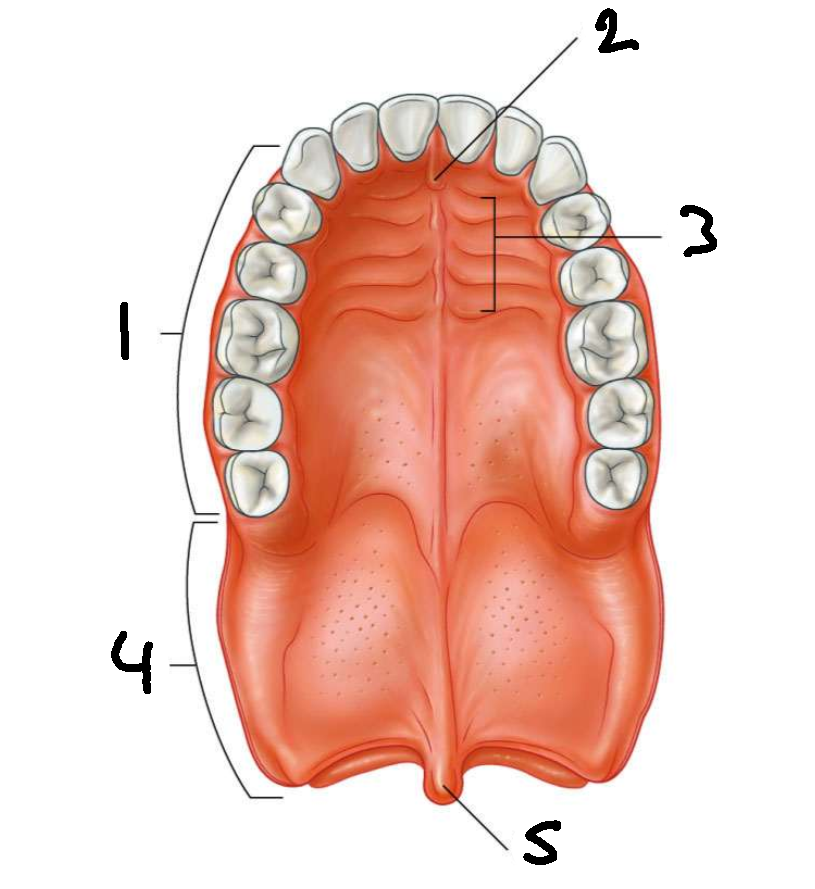

What is 1?

hard palate

What is 2?

incisive papilla

What is 3?

palatine rugae

What is 4?

soft palate

What is 5?

uvula